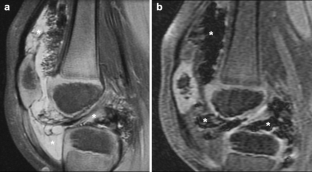

Synovium is the thin membranous lining of a joint. It produces synovial fluid, which lubricates and nourishes the cartilage and bone in the joint capsule. Synovial diseases in children can be classified as normal structures as potential sources of pathology (synovial folds: plicae, infrapatellar fat pad clefts), noninfectious synovial proliferation (juvenile idiopathic arthritis, hemophilic arthropathy, lipoma arborescens, synovial osteochondromatosis, pigmented villonodular synovitis, reactive synovitis), infectious synovial proliferation (pyogenic arthritis, tuberculous arthritis), deposition disease (gouty arthropathy), vascular malformation, malignancy (metastasis) and intra-/periarticular cysts and cyst-like structures. Other intra-articular neoplasms, such as intra-articular synovial sarcoma, can mimic synovial disease in children.

Fig. 4